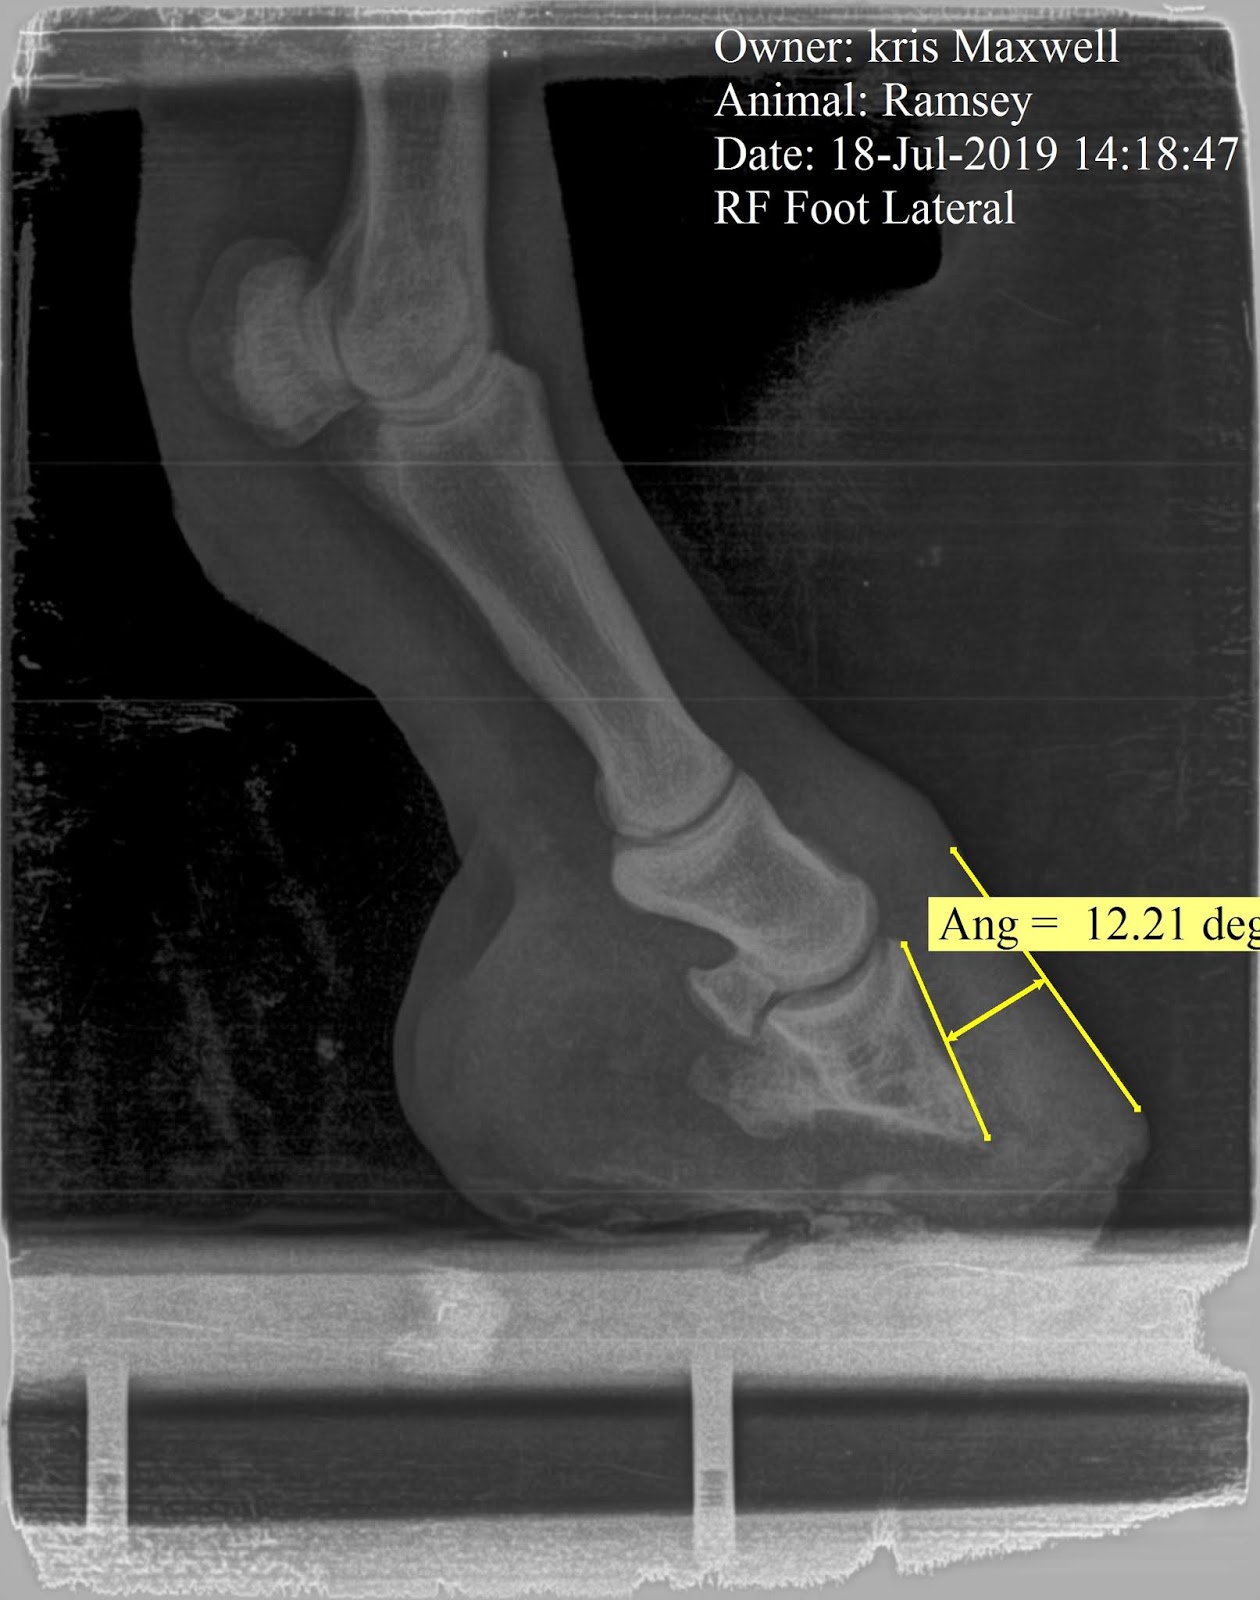

These bones should all have a smooth whitish appearance. The part that looks like cottage cheese is what is left of Ramsey's coffin bone.

In addition to the bone loss, the coffin bone has also rotated by 12 degrees. This is laminitis caused by a lack of good wall connection, which is itself caused by the bone loss, which will cause more separation......